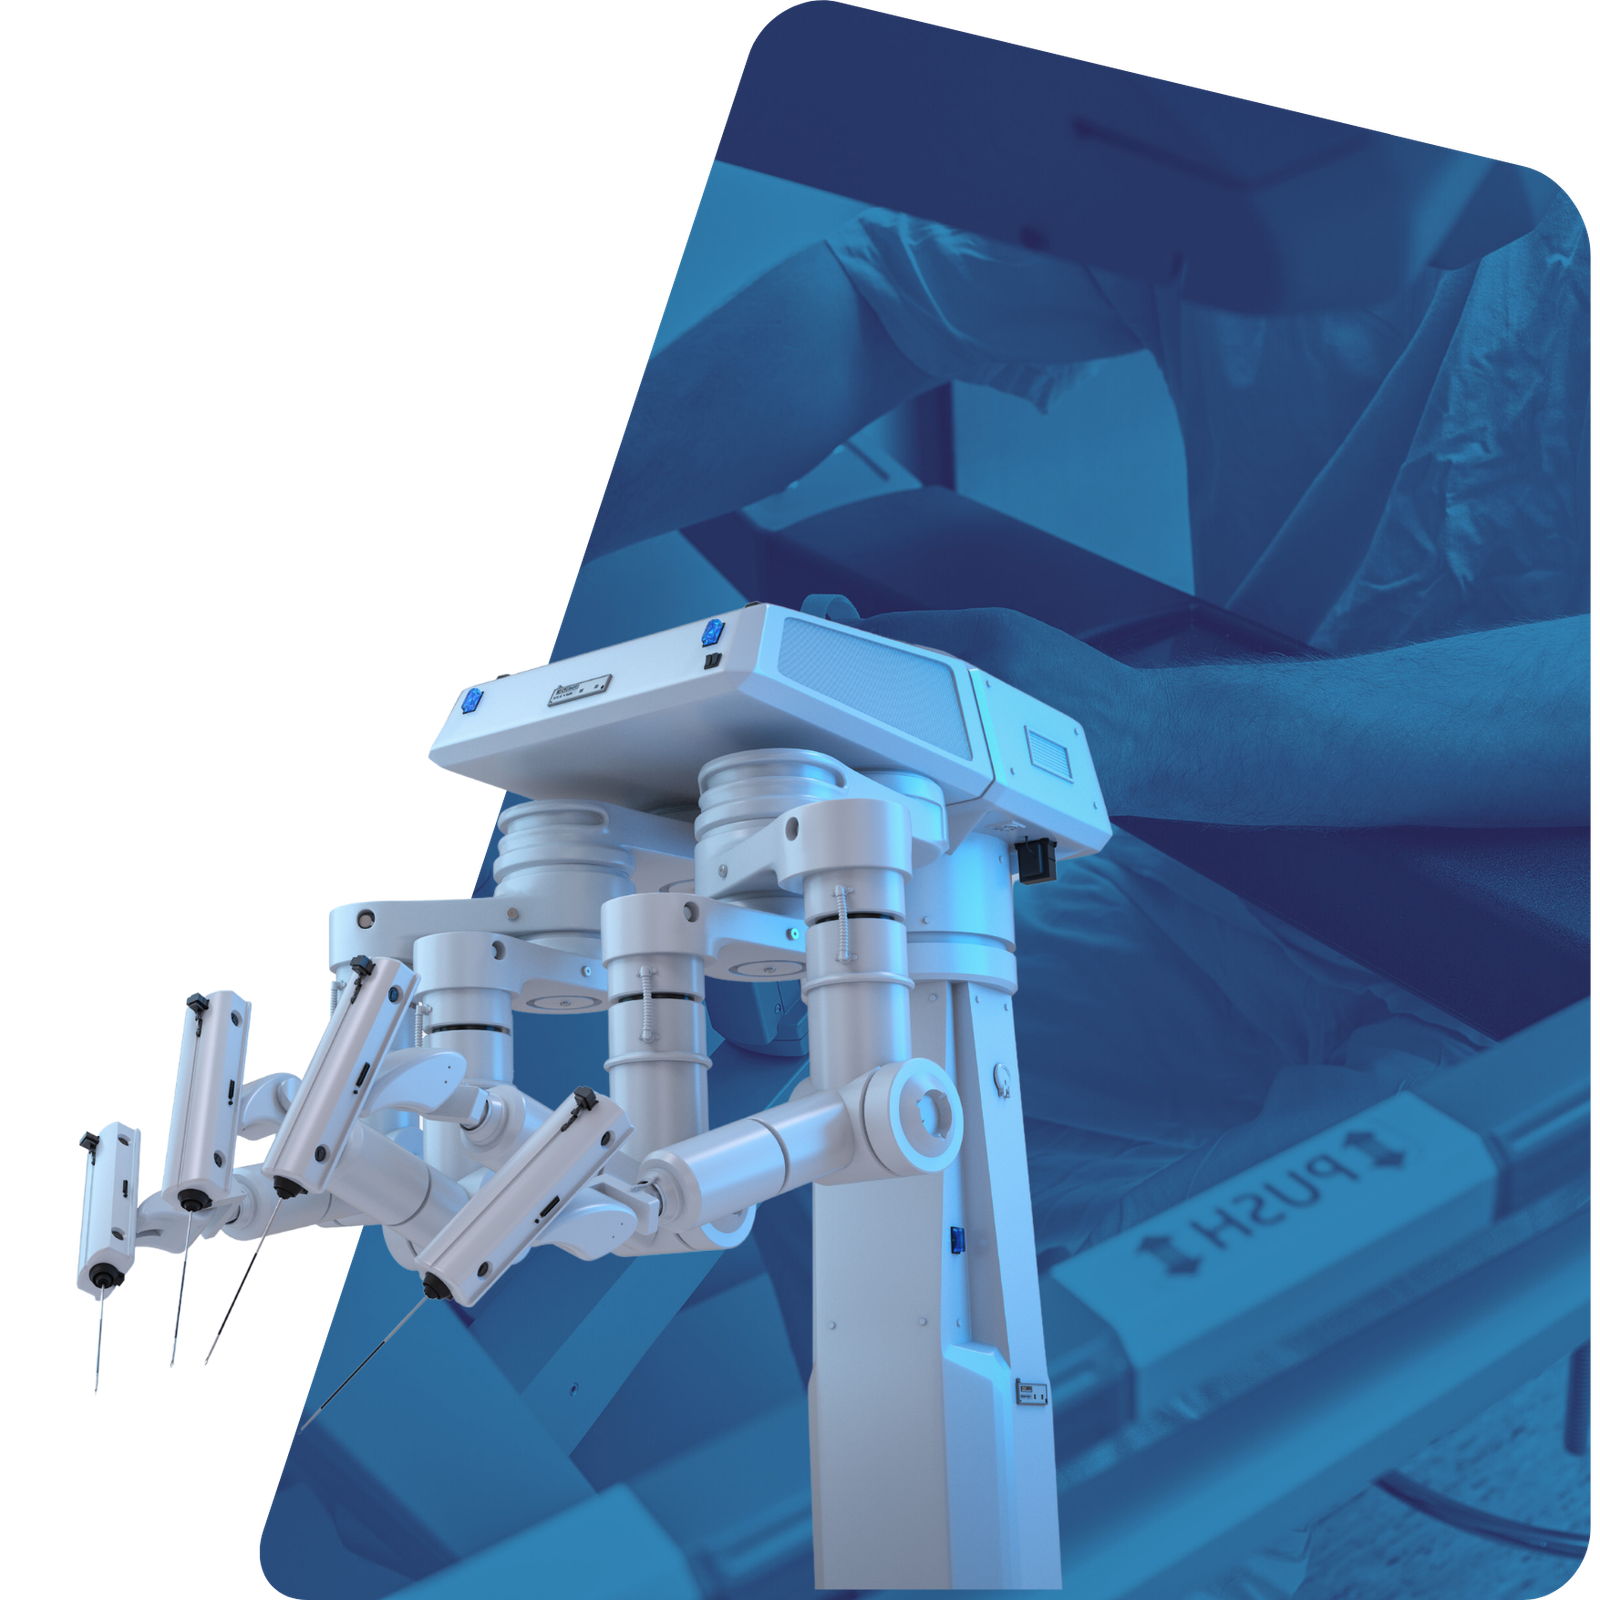

Cirurgia Robótica

A cirurgia robótica é a mais moderna técnica cirúrgica utilizada em procedimentos urológicos, oferecendo alta precisão e menos invasividade. Com o auxílio do sistema robótico, o cirurgião tem visão ampliada em 3D e movimentos mais delicados, proporcionando resultados superiores.

Principais indicações:

- Câncer de próstata

- Câncer de rim

- Cirurgias para reconstrução do trato urinário

- Tratamento de estreitamentos e anomalias urológicas

Benefícios:

- Menor sangramento e menor risco de complicações

- Precisão milimétrica nos movimentos cirúrgicos

- Menos dor no pós-operatório

- Recuperação mais rápida e alta hospitalar precoce

- Menor impacto na função urinária e sexual